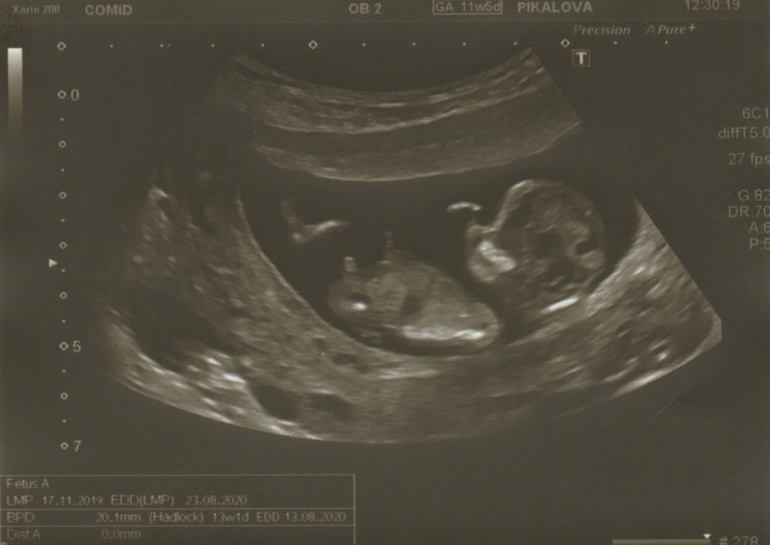

Всем Привет Девочки!🙂 У нас 13 недель, сказали что мальчик... посмотрите по фото, что скажите) Честн

Спасибо за ответ🌷😊 Блин.. многие пишут, что мальчик... точно настроюсь на мальчика😁 думаю всё равно рановато, надо дождаться следующее узи) а так вообще не понимаю, как определяют.. вижу только маленький бугорочек, как можно по нему определить.. не понимаю🤷🏻♀️

Вот так)) У вас видно прям наверх устремлен, если это он конечно))) У нас совпало, уже в 11 недель даже видели))

Нам в 12 сказали-показали, в 14 и далее подтвердили. Видите пимпочку?) 12 недель

Не видно на этом фото, честно говоря... Немного бы влево сместить кадр.

Ну, я фотку Вашу с узи отдельно открыла... Увидела, что как бы торчит вверх больше - значит, мальчик)) Но сомневаюсь - возможно, это ножка, а за ней бугорок, который не видно.

Спасибо за ответ👏🏻 А так вообще не понятно, кто будет? Нам сказали, что у нас бугорочек не так, как у девочек.. у девочек так не бывает

Подождите до недель 16 хотябы, рано ещё в 13... На таком сроке путают часто. В 16 уже точно сказать смогут, если малыш покажет.